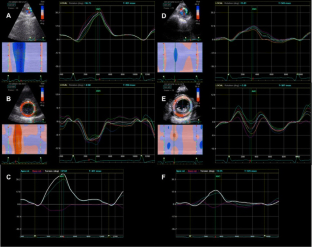

Fig. 1

Fig. 2

Fig. 3

Fig. 4

Fig. 5

Fig. 6

Fig. 7